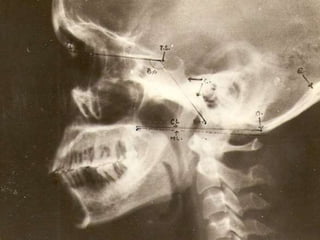

CRANIOMETRY

• Craniometry -series of lines, planes & angles to define the normal

anatomic relationships of the CVJ.

• These measurements can be taken on plain X rays, 3D CT or on MRI.

• No single measurement is helpful.

• Disadvantage --anatomic structures and planes vary within a normal

1.Nasion

2.Tuberculum sella

3.Basion (anterior

Margin of the

Foramen magnum)

4. Opisthion

(Posterior margin of

The foramen

Magnum)

5. Posterior pole of

The hard

Palate

6. Anterior arch of

The atlas

7. Posterior arch of

8. Odontoid process

Lines,angles radiologic diagnosis of C.V